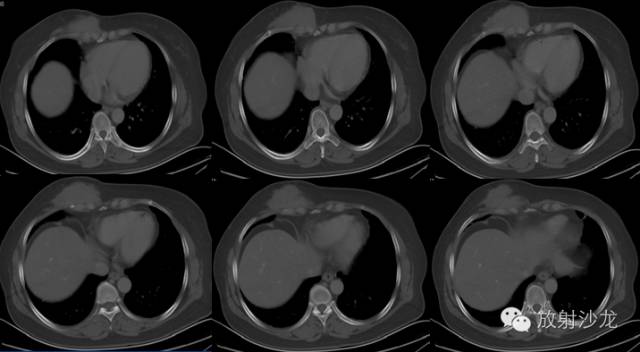

CT表现:CT对侵袭性纤维瘤病的诊断无特异性,CT常表现为肿瘤沿肌肉长轴生长,边缘规则或不规则,密度基本均匀,增强扫描可见强化。CT扫描能提示病变的性质并能正确评价病变侵犯的范围,对制订恰当的治疗方案及减少复发机会有明显价值口。

韧带样纤维瘤按其生长部位不同,可分为腹壁和腹壁外韧带样纤维瘤,病因尚不完全清楚,其发生可能与创伤、内分泌和遗传等因素有关。该肿瘤在生物学行为上属于中间类型,常局部复发但罕见转移,手术切除是韧带样纤维瘤最有效的治疗方法,有文献报道其术后复发率为15%~77%,切缘阳性者明显高于切缘阴性者。

韧带样纤维瘤发病率低,有关该肿瘤治疗效果的报道均为回顾性研究,国内外尚缺乏统一的治疗指南。完整切除肿瘤是首选的治疗措施,但该类肿瘤质地坚硬,常呈局部浸润性生长,无包膜形成,通过肉眼常难以判断肿瘤所累及的范围,且胸部神经、血管丰富,有时要达到切缘阴性并非易事。由于该肿瘤与一般恶性肿瘤不同,其一般不会危及生命且罕见恶变,所以对于肿瘤侵犯肢体及重要组织器官,无法完整切除的患者,可考虑行姑息性切除 术后放疗,不能片面的追求切缘阴性而牺牲患者肢体及重要器官的功能。对完整切除后复发的患者,二次手术或多次手术也可获得良好疗效